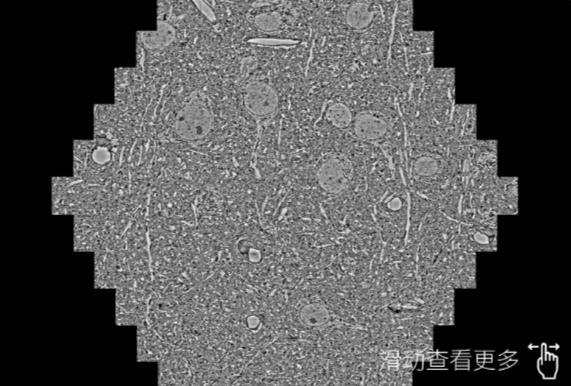

鼠脑切片。左图使用通辽蔡司通辽扫描电镜MultiSEM706对165μmx143pm面积区域成像,耗时仅需1.5秒。右图为鼠脑切片中30μm区域放大效果。样品由芝加哥大学B.Kasthuri提供。

使用蔡司高速通辽扫描电镜MultiSEM对1mm²人脑皮层组织进行高分辨成像,并对其中的各种细胞结构进行三维重构分析。左图展示了2x3mm²组织平面中锥体神经元的三维重构效果。右图显示了局部体积神经元三维重构。图像由哈佛大学chtman实验室提供,渲染图由D. Berger 制作。